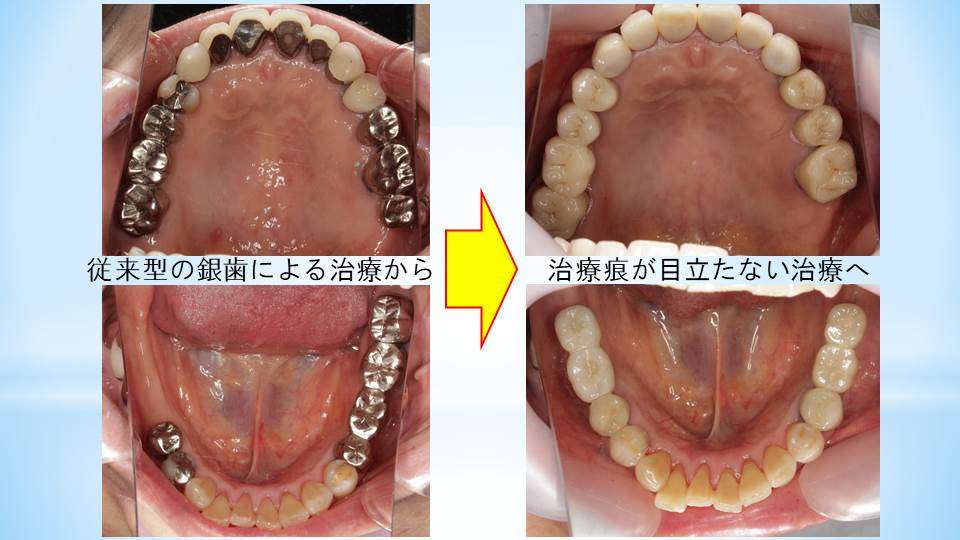

皆様はもし仮に、医科の手術として開腹手術を受けた場合、傷跡は出来るだけ残さないようにして欲しいと考えませんでしょうか?歯科では長らく、銀歯で治療痕を残す治療が、歯科医師の手により平気でなされてきました。医療用生体材料と技術の飛躍的な進歩により、現代の歯科治療は可能な限り治療痕を残さない治療にシフトしています。写真の症例では、治療後には金属色は全く見えないように治療されています。